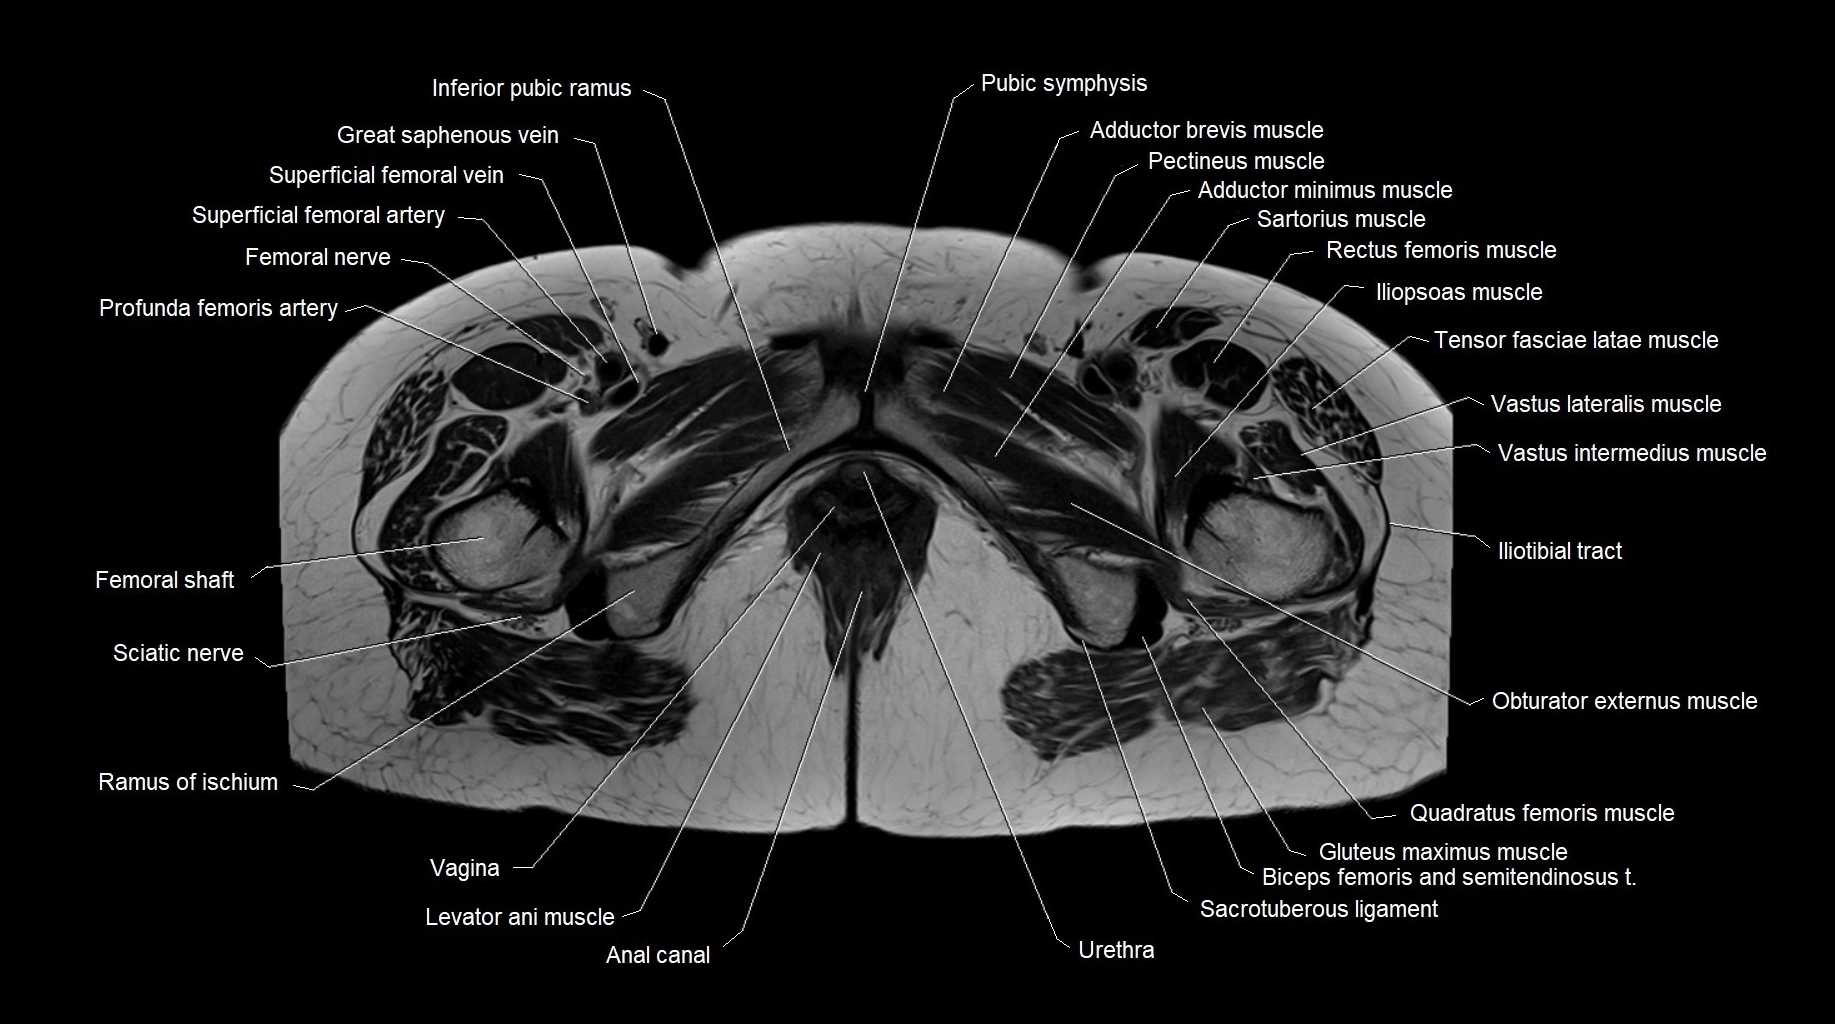

- Anal canal

- Femoral nerve

- Femoral shaft

- Inferior pubic ramus

- Levator ani muscle

- Obturator externus muscle

- Pubic symphysis

- Quadratus femoris muscle

- Ramus of ischium

- Sacrotuberous ligament

- Sciatic nerve

- Vagina

- great saphenous vein